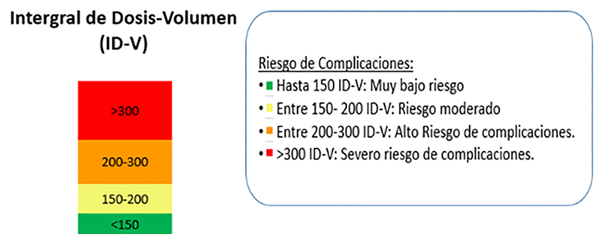

Otro factor decisivo a la hora de considerar la seguridad de la Radiocirugía es conocer la limitante de dosis. En los casos de las MAV´s intrincadas en medio del parénquima cerebral, la misma se define utilizando un parámetro denominado Integral de Dosis: que relaciona volumen con dosis. (Figuras 1 y 2)

Figura 2: Gráfico que expresa el riesgo de complicaciones en función de la “Integral de dosis-volumen”